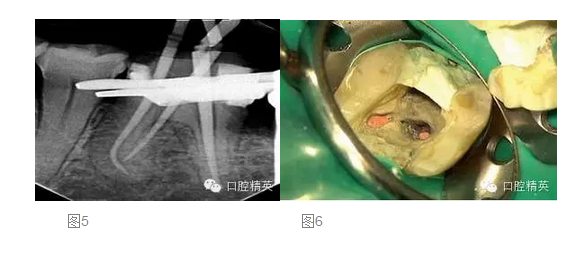

在第二次就診時(shí),我們?cè)俅芜M(jìn)行抗菌的根管沖洗,然后使用消毒的紙尖擦干根管。將牙膠尖置于根管內(nèi),拍攝主尖片(圖 5)。根充糊劑為AHPlus(DENTSPLY DeTrey)。根管充填過(guò)程中,使用System B及連續(xù)波加壓技術(shù)對(duì)根尖4mm進(jìn)行根管充填,回填過(guò)程使用Obtura III Max 的熱塑牙膠(Obtura Spartan)。

在根管充填過(guò)程中,要非常小心不要將根充糊劑壓入根管側(cè)穿的部位。對(duì)近中舌根的回填置于穿孔的根尖方向(圖 6)。根管充填后,使用MTA 輸送器(同樣也是DENTSPLY Maillefer 公司)對(duì)側(cè)穿部位進(jìn)行MTA修補(bǔ),封閉穿孔的部位。正如轉(zhuǎn)診醫(yī)生所要求的,遠(yuǎn)中根管內(nèi)為預(yù)留樁的空間,轉(zhuǎn)診醫(yī)生打算自己進(jìn)行樁道預(yù)備,以放置能夠放射顯影的樹脂樁(圖 7)。使用Cavil G(3MESPE公司)作為冠部的暫封材料。最后叮囑患者復(fù)診以最終修復(fù)患牙,同時(shí)6個(gè)月后進(jìn)行復(fù)查。